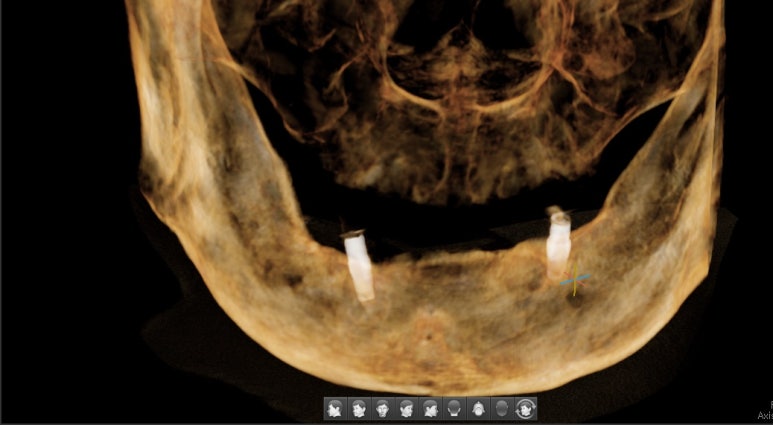

7.아래쪽 임플란트 최소 2개 심고 틀니 연결하여

덜 움직이는 틀니

8.다른 치과에서 한 아래틀니가 너무 아픈 환자분

아래 2개 임플란트를 심고 임플란트 틀니로 변경

아래치아 하나도 없음. 임플란트 심기 전

↓

아래 임플란트틀니를 위한 임플란트 2개 식립

기존 다른치과 전체틀니에 임플란트를 연결하여 움직이지 않게 해드렸습니다.